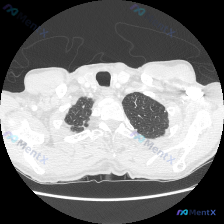

看到一个胸部CT肺窗病例,整理了一下分析思路,大家一起讨论。 主诉与现病史:无直接提供,但从影像来看有局灶性病变。 检查/检验:本次提供的是胸部CT肺窗横断面图像,清晰度良好,无明显伪影。 影像信息:层面约在主动脉弓水平,气管居中,双肺透亮度大致对称。右肺(图像左侧)上叶可见多发性囊泡状、网格状透亮...

看到一个胸部CT肺窗的病例资料,整理了一下分析思路,分享给大家讨论。 病例基本信息 患者无明确临床症状(输入中未提及),影像检查显示右肺尖部异常改变。 影像特征分析 这是一张胸部CT肺窗横断面图像,层面位于胸廓入口水平,显示双侧肺尖部: 1. 右肺尖(图像左侧): 可见弥漫性囊腔状、蜂窝状透亮影,伴...